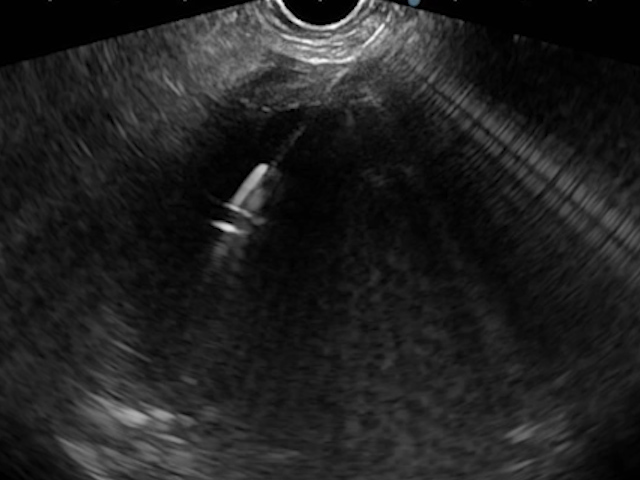

An EUS-guided CGA was performed using a plastic pigtail stent. Under deep sedation and endotracheal intubation, the collection was punctured with a 19G FNA needle, and the aspirate, with a brownish appearance typical of a pseudocyst, was sent for biochemical and microbiological analysis (Fig. 4).